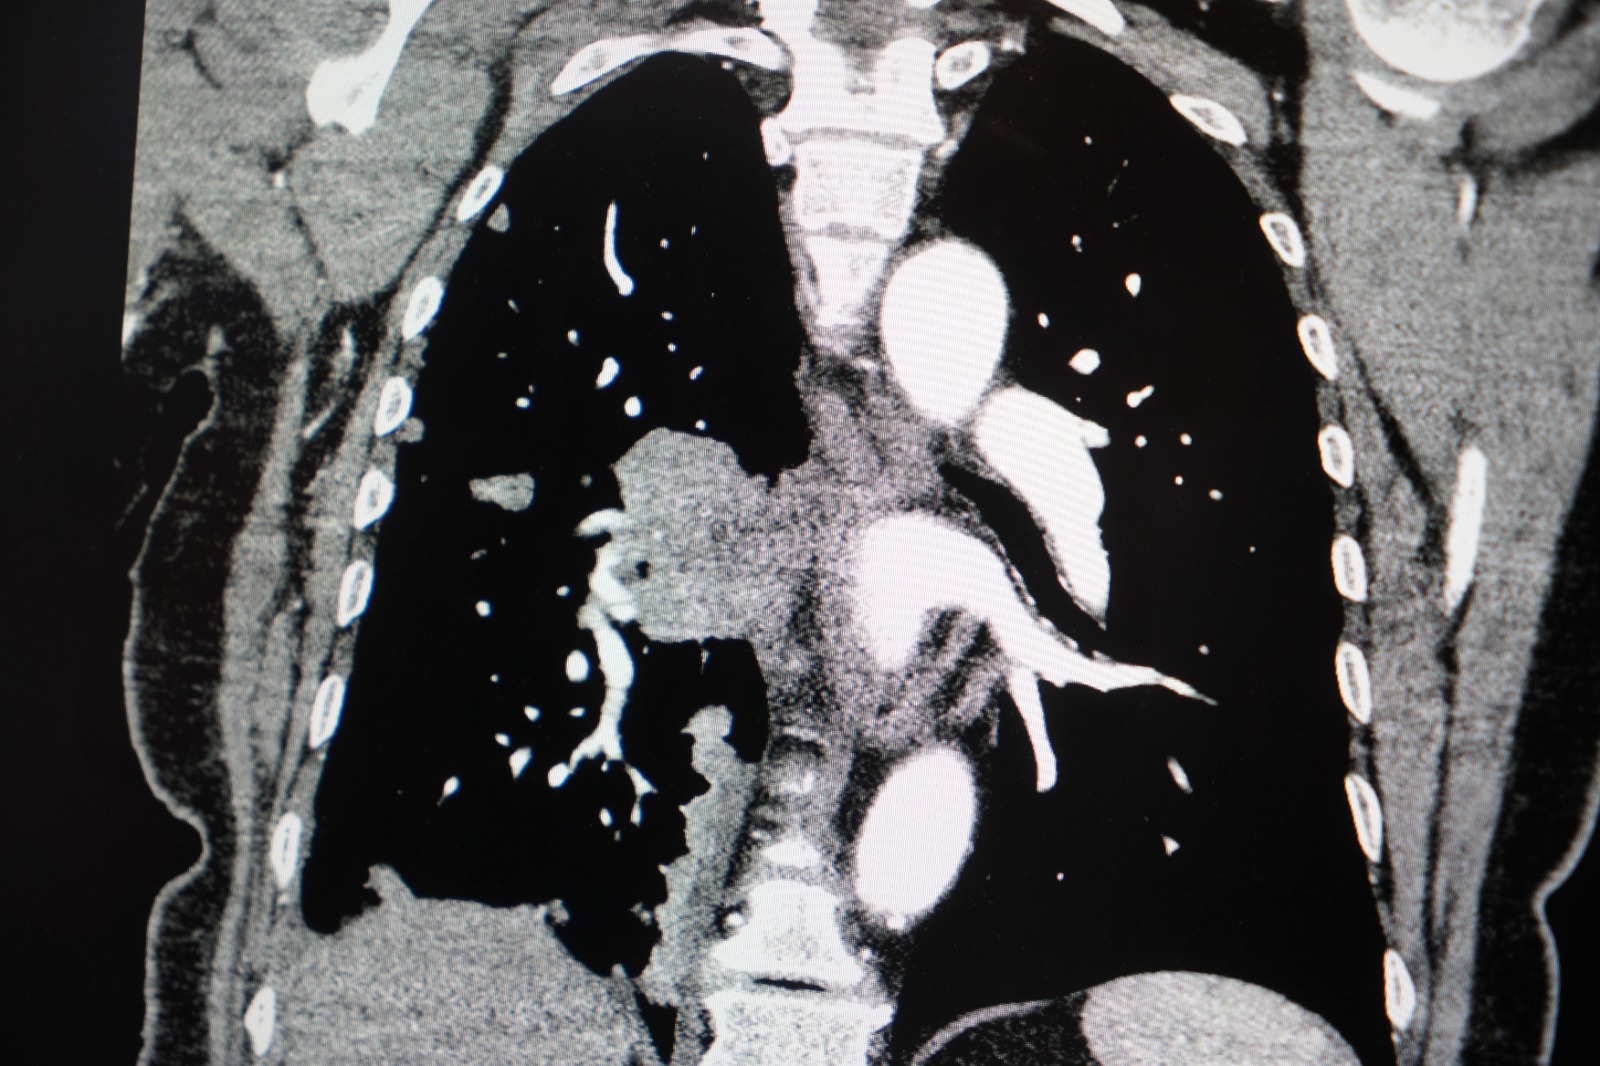

"KADINLARDA AKCİĞER KANSERİ VAKALARI BELİRGİN ŞEKİLDE ARTIYOR"

Akciğer kanseri vakalarındaki artışa da dikkat çeken Özkaya, "Son yıllarda hem sigara içen hem de hiç sigara kullanmamış bireylerde akciğer kanseri vakalarında dikkat çekici bir artış görüyoruz. Özellikle kadınlarda adenokarsinom tipi akciğer kanseri belirgin şekilde artış göstermektedir., Yapılan son araştırmalara göre akciğer kanseri teşhislerinin yaklaşık yüzde 20'si hiç sigara içmemiş bireylerde konuluyor. Bunun en önemli nedeni pasif içiciliktir. Yani siz sigara içmeseniz bile, yakın çevrenizde sigara içiliyorsa akciğer kanseri riskiyle karşı karşıya kalabilirsiniz" ifadelerini kullandı.